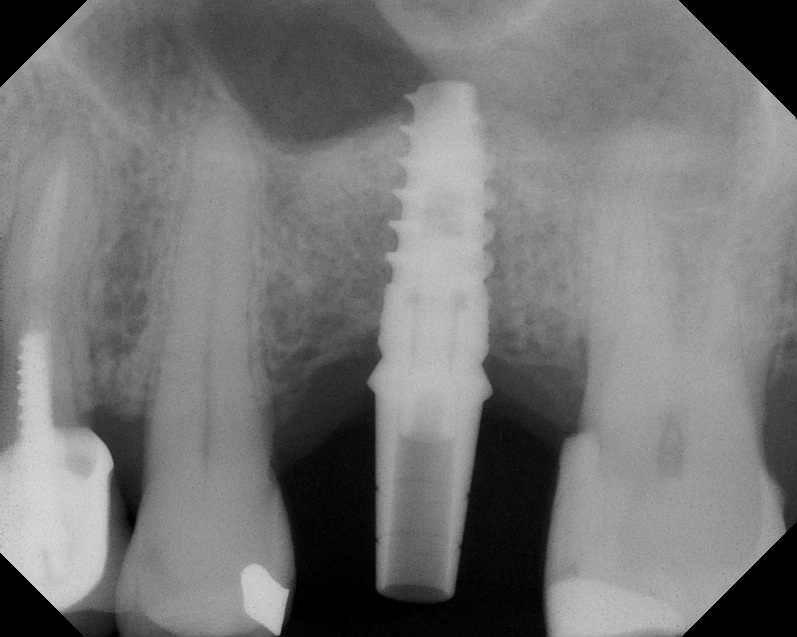

Radiograph of implant N o. 3 and sinus augmentation, day of placement. There is about 2 mm to 3 mm of native bone, and the sinus has been raised about 8 mm to 9 mm.

Fig. 10

A 7-month postoperative radiograph of the restored implant No. 3.

Fig. 11

CBCT scan (Kodak 9000D) showing 3.5-month postoperative of implant No. 3 in place. Note homogeneous appearance of the bone.

Fig. 12

The implant is then delivered and should be well stabilized in the bone. If there is any mobility of the implant, it can either be placed a little deeper (if there is enough native bone) or the implant can be removed and the procedure aborted, in which case it would be a two-stage procedure. This should rarely occur with the tapered designed implant, even with only 2 mm of native bone. Using a bone-level platform-shifting implant (or a tissue-level designed implant) is critical, as the hard and soft tissue will establish a biologic width. If an external hex type of implant is used and the shoulder is placed at the bone level, an expected bone loss of 1.5 mm to 2 mm will occur.24 Figure 10 shows proper bone-level implant depth placement with a platform-shifting design. In this case, a 3-mm healing abutment was placed at the time of surgery to avoid a secondary uncovering surgery, but an implant-level healing abutment could have been placed instead. As can be seen, there was only about 2 mm to 3 mm of native bone height. The membrane was raised about 8 mm to 9 mm. Comparing the radiograph on the day of surgery (Figure 10) to the 6-month postoperative radiograph (Figure 11) shows no loss of native bone, as well as the positive change in appearance of the grafted bone. The 3.5-month CBCT scan (Figure 12) shows good healing of the bone with no coronal bone loss. With minimal native bone present, as in this case, the use of a non-platform-shifting or non-tissue-level implant design could be problematic. After 1.5 mm to 2 mm of crestal bone loss, an external hex designed implant could develop instability with possible implant failure. If a non-tapered implant is used and bone loss occurs during healing, migration of the implant into the sinus could potentially occur. The surgeon can use either a healing abutment or implant-level closure screw over the implant shoulder. With patients who tend to use their tongues to explore or play with the area, or if the area is under a removable partial denture, a closure screw is recommended.